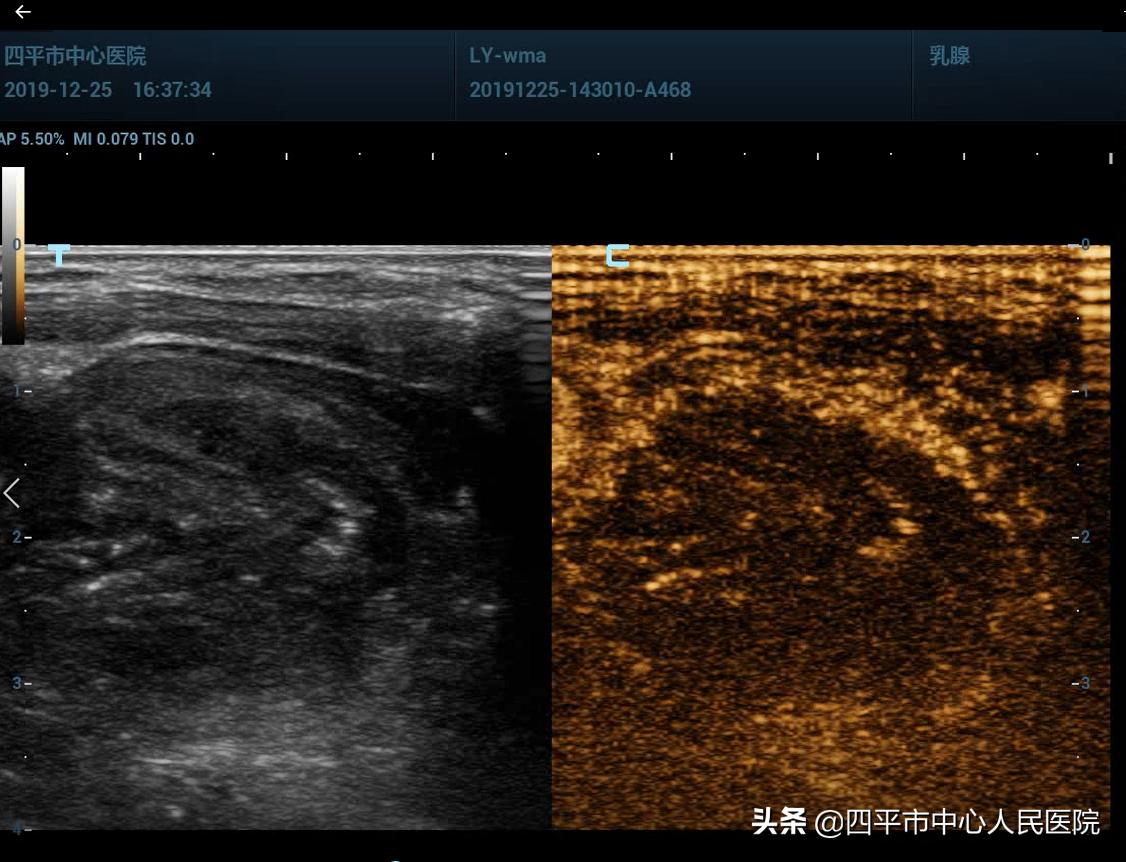

术中,局麻后,首先对结节内囊性部分进行抽吸酒精硬化治疗,然后置入微波消融针进行多点多切面消融,消融频率25W,消融后即刻进行超声造影,明确消融效果,造影显示消融区域未见明显强化,消融效果良好。

消融后即刻造影显示消融区域少许强化,再次消融